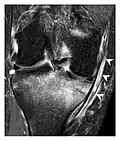

Figure 13: Partial osseous avulsion of the gluteal muscles at the greater trochanter in a 59-year-old man who presented with the right hip pain without a history of trauma. Lauenstein view and anteroposterior and radiographs (not shown) did not show an obvious fracture line or disruption of bony contours in the acetabulum or the right femoral neck. (a) Coronal T1-weighted MRI displays an incomplete fracture line extending partially from the greater trochanter (arrow). (b) Coronal short tau inversion recovery MRI shows heterogeneous hyperintensity in the same region (arrow) as well as hyperintensity within the gluteus medius and minimus muscles (arrowheads) consistent with tissue edema and hematoma.[1]

Figure 14: Subcapital insufficiency fracture in a 55-year-old man with a left hip pain without a history of trauma. Anteroposterior and Lauenstein view radiographs centered on the left hip do not show an obvious fracture line, but mild acetabular osteophytosis was noted consistent with hip osteoarthritis (not shown). (a) Coronal T1-weighted MRI shows a linear low-signal band through the femoral neck corresponding to a fracture line (arrowheads). (b) Bone scintigraphy shows focal uptake (arrow) corresponding to the fracture.[1]